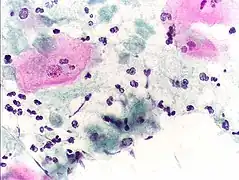

Diagnosis

Classically, with a cervical smear, infected women may have a transparent "halo" around their superficial cell nucleus but more typically the organism itself is seen with a slight cyanophilic tinge, faint eccentric nuclei, and fine acidophilic granules.[30] It is unreliably detected by studying a genital discharge or with a cervical smear because of their low sensitivity. T. vaginalis is also routinely diagnosed via a wet mount, in which "corkscrew" motility is observed. Currently, the most common method of diagnosis is via overnight culture,[31][32] with a sensitivity range of 75–95%.[33] Newer methods, such as rapid antigen testing and transcription-mediated amplification, have even greater sensitivity, but are not in widespread use.[33] The presence of T. vaginalis can also be diagnosed by PCR, using primers specific for GENBANK/L23861.[34]

Pap smear, showing infection by Trichomonas vaginalis. Papanicolaou stain